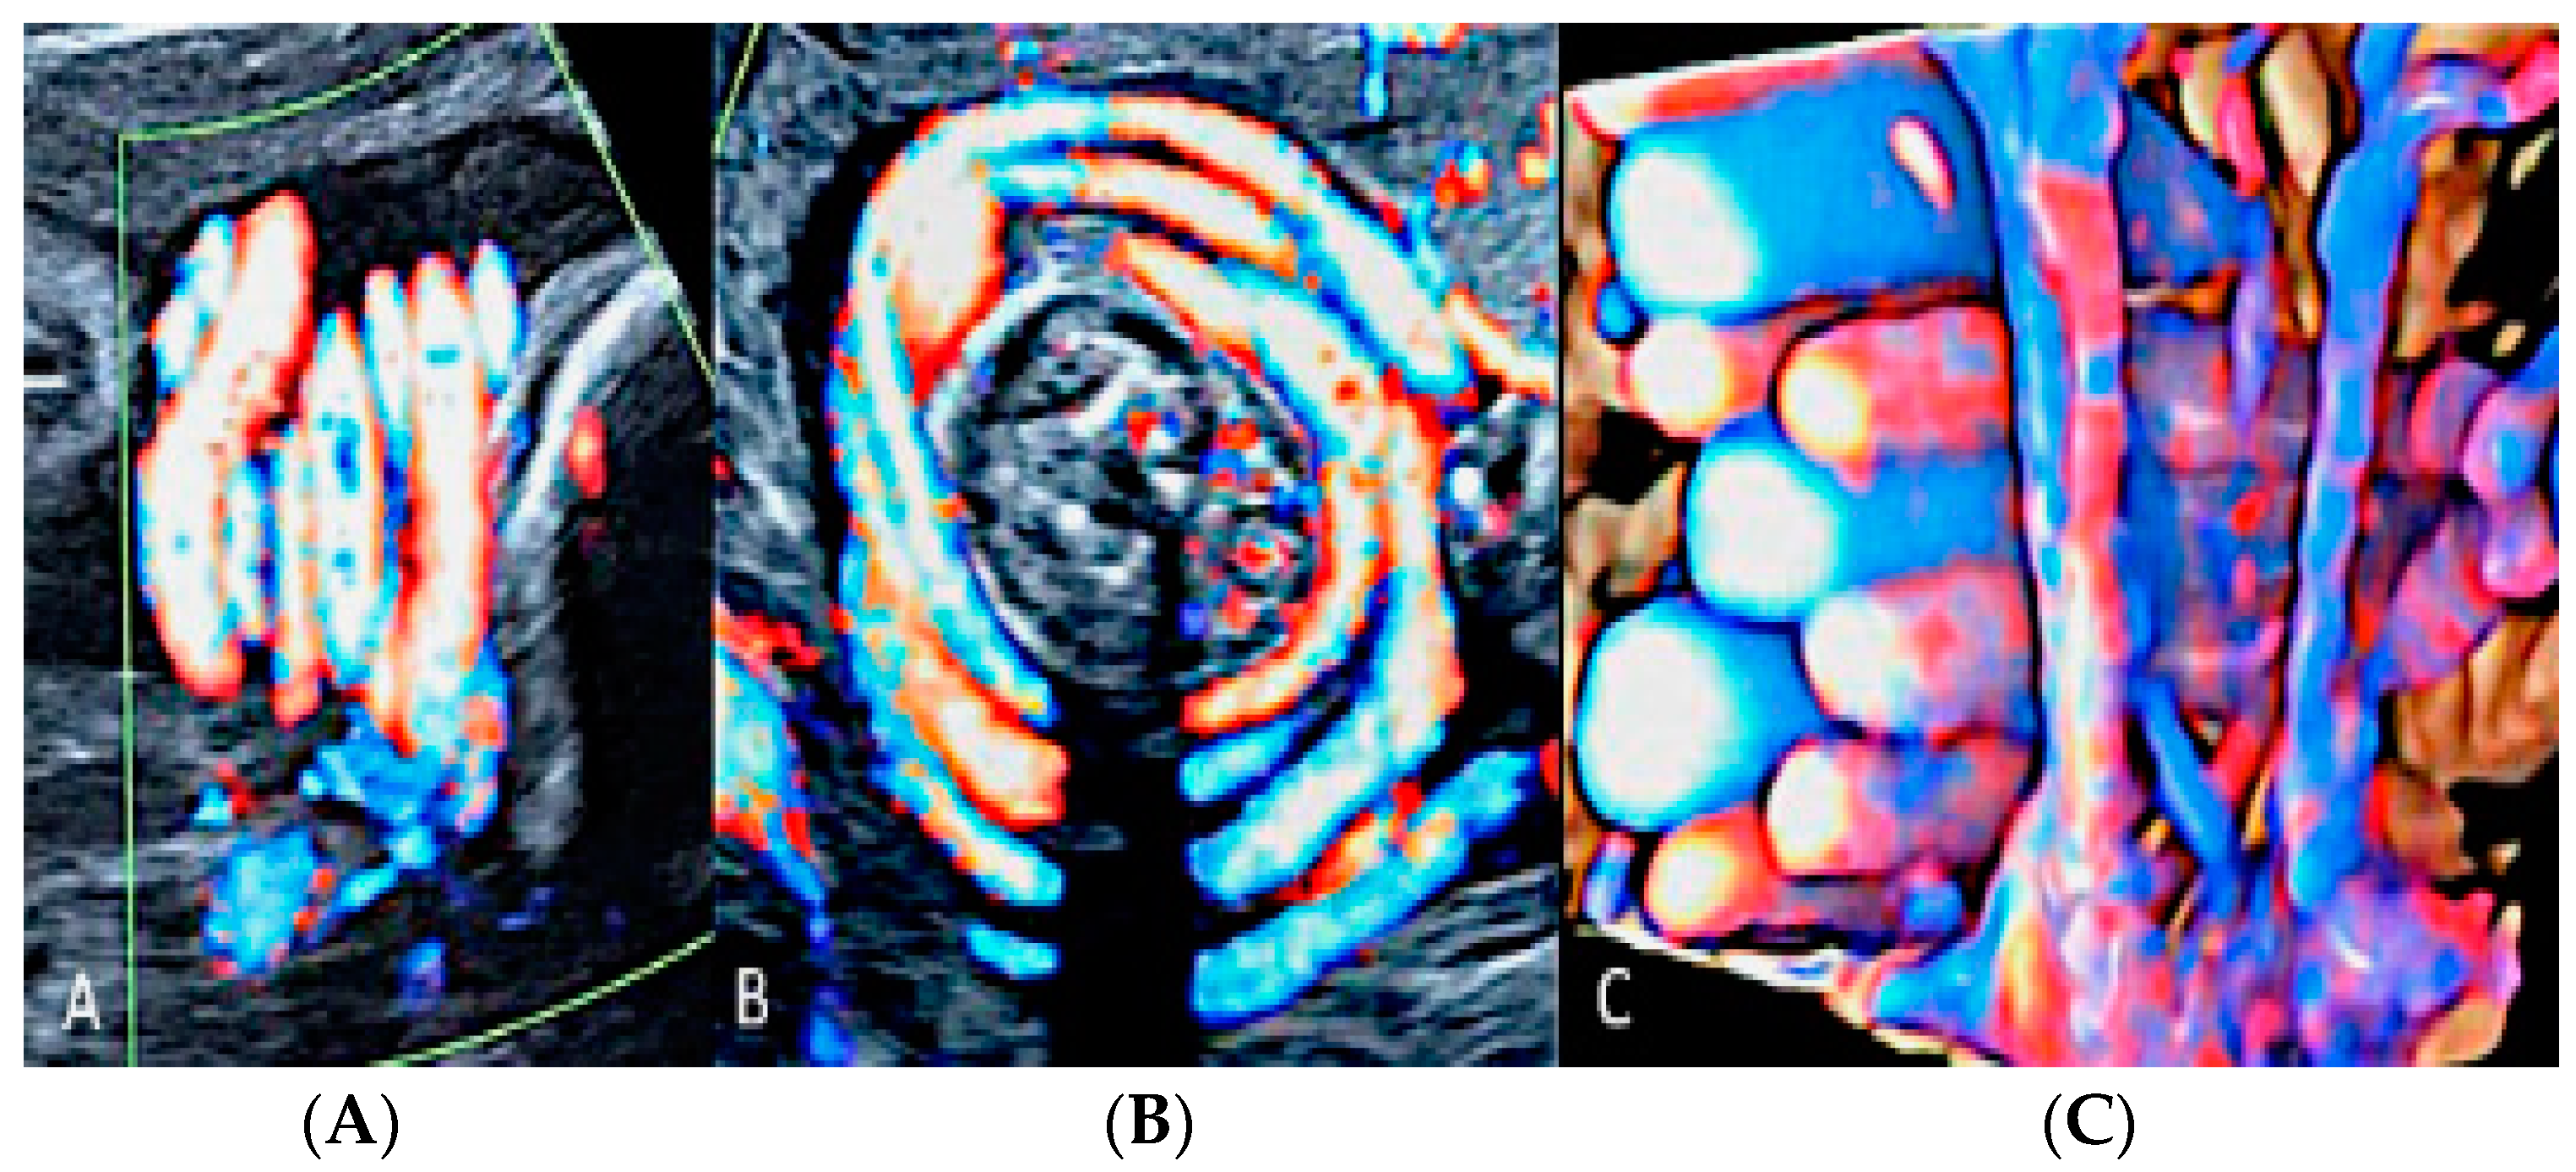

3.2.1. Nuchal Cords

A nuchal cord occurs when the umbilical cord becomes entangled at 360 degrees around the fetal neck [44,45]. The prevalence of nuchal cords at birth is around 22% of all pregnancies [4], with no significant statistical association between the presence of a nuchal cord and stillbirth [4,5]. On the other hand, multiple loops of nuchal cord have been associated with abnormal fetal heart rate pattern during labor, low umbilical artery pH, an increased likelihood of Cesarean section or operative deliveries and an Apgar score < 7 at the 5th minute [4,46]. Tight nuchal loops are associated with a low Apgar score but not with an increased admission to the neonatal intensive care unit (NICU). Loose loops of nuchal cord are associated with a favorable in utero prognosis and perinatal outcome [4] (Figure 15).

Figure 15.

Two-dimensional ultrasound using color Doppler ultrasound and three-dimensional ultrasound with STIC color Doppler and “glass body” mode rendering with HD-Live™ flow showing multiple loops of cord around the neck in sagittal (A), axial (B) and coronal scans (C), resembling a “whirlpool” sign.